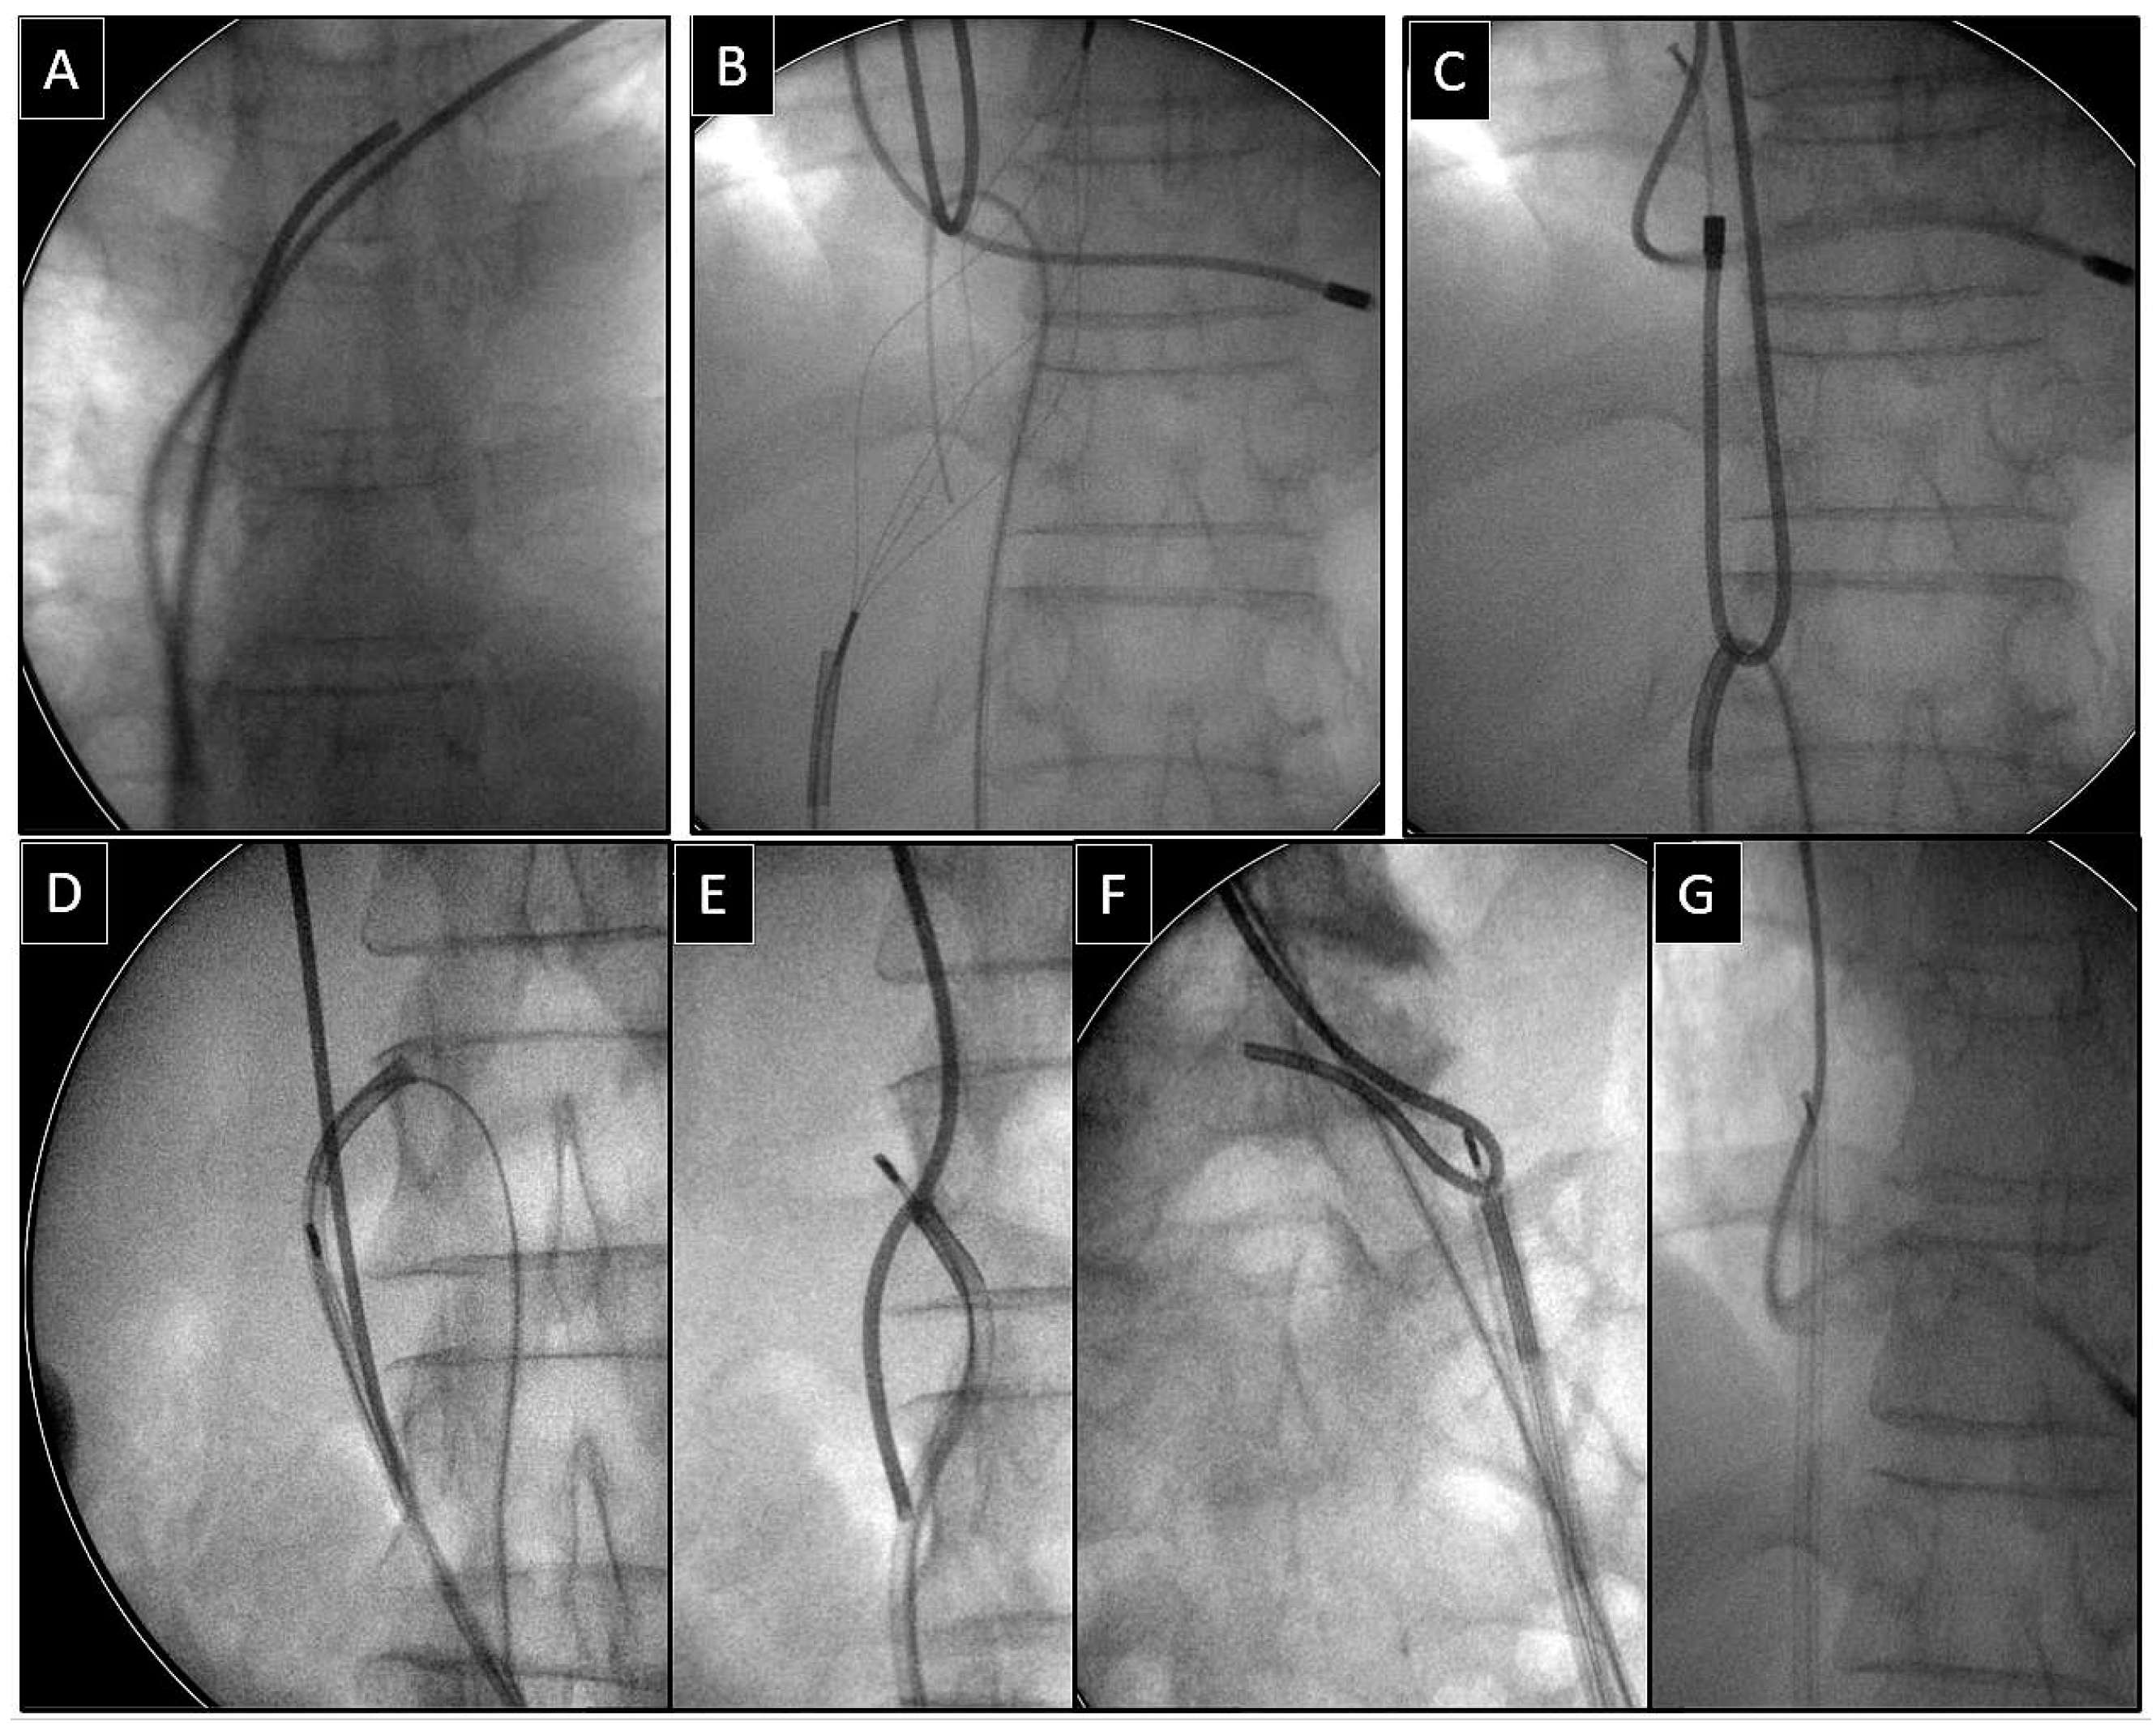

Extraction of Leads with Migrated Proximal Ends into the Cardiovascular Space

- Removal of such leads requires the use of different approaches and dedicated and non-dedicated tools.

| Superior approach | 6 (15.39) | 3 (23.08) p = 0.832 | 3 (23.08) p = 0.832 | 5 (71.43) p = 0.007 | 17 (23.61) |

| Combined approach | 3 (7.69) | 3 (23.08) p = 0.316 | 1 (7.67) p = 0.548 | 1 (14.29) p = 0.874 | 8 (11.11) |

| Femoral approach | 29 (74.36) | 7 (53.85) p = 0.298 | 8 (61.54) p = 0.596 | 1 (14.29) p = 0.001 | 45 (62.50) |

| Lasso/basket inside 13 FWS, NE (dilatation) | 31 (68.89) | Lasso/basket 13, FWS, NE—femoral approach (dilatation) | 31 (43.06) |

| Lasso/basket inside another large sheath (polypropylene) (dilatation) | 5 (11.11) | ||

| Lasso/basket inside transseptal sheath (only pulling) | 9 (20.00) | Lasso/basket another large sheath—femoral (dilatation) | 5 (8.33) |

| Loop femoral approach (pulling, end release) | 35 (77.78) | Lasso/basket in CS sheath—superior approach (pulling only) | 1 (1.39) |

| Pig-tail + winding and shifting femoral (end release) | 7 (15.56) | Lasso/basket only—superior approach (pulling only) | 3 (4.17) |

| Pig-tail femoral (end orientation) | 3 (6.67) | Cardiac surgery | 2 (2.28) |